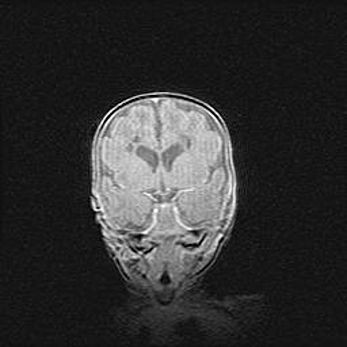

Аномалия Денди-Уокера. Признаки гипоплазии мозолистого тела.

Возраст: 5 месяцев 3 дня

Вес: 5550 г

Пол: мужской

Окружность головы: 39 см

Срок гестации: 40 недель

Аномалия Денди-Уокера – это порок развития головного мозга, для которого характерна триада симптомов: гипотрофия или аплазия червя мозжечка и/или полушарий мозжечка, расширение четвёртого желудочка с формированием ликворной кисты задней черепной ямки, гипертензионная гидроцефалия различной степени.

Гипоплазия мозолистого тела относится к дефектам внутриутробного этапа развития мозговой ткани, возникающим в процессе закладки структур головного мозга, что происходит на начальных этапах развития эмбриона.